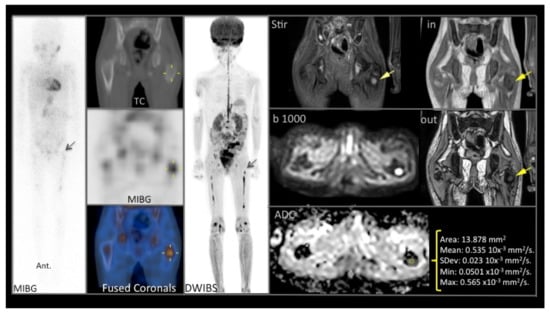

Figure 3 shows the chemorefractory femur lesion before naxitamab-based chemo-immunotherapy for patient #13 (Table 1). After 8 HITS cycles, the persistent MIBG+ lesion was biopsied showing GN (see below).

Figure 3.

Example of a good correlation between proximal left femoral metaphysis 123I-Metaiodobenzylguanidine (MIBG) bone uptake (left column) and MRI/DW (middle and right panels) for patient #13 (Table 1), showing T1 hypointense, STIR T2 hyperintense focal bone lesion with restricted diffusion (b 1000), and low ADC (<1.01) values.

Patient #1 (Table 1) received naxitamab and GM-CSF for primary refractory neuroblastoma in multiple bones. After 4 cycles only, one iliac bone lesion persisted positive on MIBG. PET-FDG was negative and DWI with high ADC is shown in Figure 4A.

Figure 4.

Correlation of functional imaging for patient #1 (Table 1) and histopathology. (A) Correlation between pre-immunotherapy treatment (top panels) functional imaging of chemo refractory iliac bone lesion and post immunotherapy evaluation (bottom panels: STIR T2 hyperintense focal iliac bone lesion with restricted diffusion -b 1000- and high- > 1.01- ADC values) of the same iliac lesion. (B) Bone tumor from patient #1 post immunotherapy. This sample shows ganglioneuromatous tissue with Schwannian stroma and some mature ganglion cells (arrow). This sample corresponds to the iliac bone lesion described by functional imaging in (A) (bottom panels). (C) S100 immunostaining highlighting the Schwannian stroma (arrow) of the same iliac bone tumor.